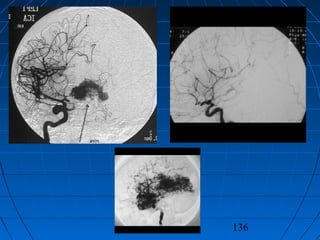

ARTERİOVENÖZ MALFORMASYONLARARTERİOVENÖZ MALFORMASYONLAR

 DDijitalijital SSubstraksiyonubstraksiyon AAnjiografisinjiografisi

135

TEDAVİTEDAVİ

 CerrahiCerrahi

 MedikalMedikal

 Girişimsel nöroradyoloji - embolizasyonGirişimsel nöroradyoloji - embolizasyon

 Radyocerrahi (gammaknife)Radyocerrahi (gammaknife)

136